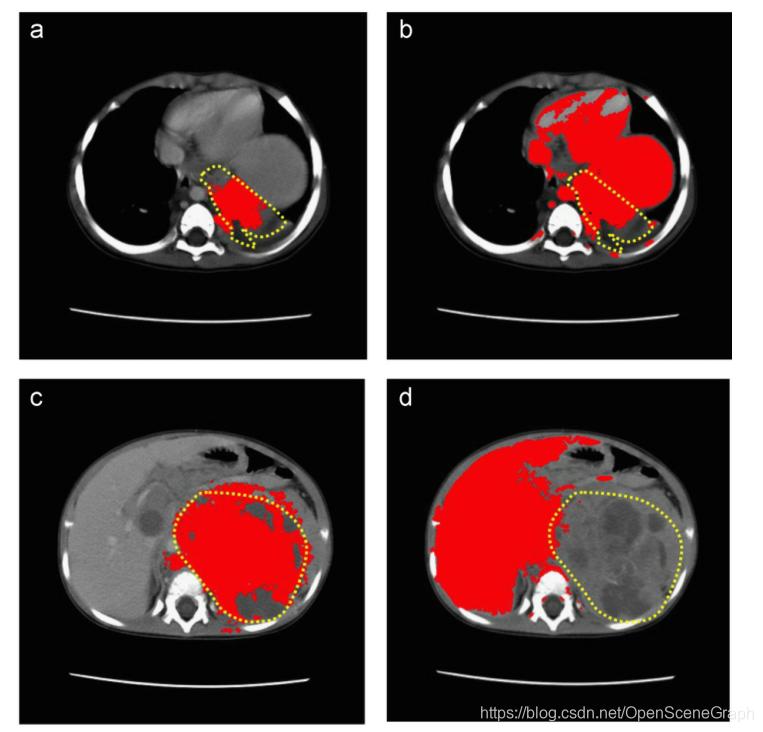

图7所示。黄色的是近似的肿瘤轮廓,红色的是实际的分割算法。灰度法选择了很多不属于肿瘤的像素,导致FP值较高。(a)数据集9灰度化,28切片,(b)数据集9灰度化,28切片,(c)数据集9灰度化,39切片,(d)数据集9灰度化,39切片。(为了解释图的说明中对颜色的引用,请参考本文的web版本。)

对于FN值越高,着色方法效果越差的两个数据集,t检验没有显著性差异。只有三个数据集对灰度法产生了更好的FN结果,在统计上有显著差异,但这些数据集对相同的数据集也给出了更高的FP值。经过仔细研究,灰度算法选择了图像中很多不属于肿瘤的像素,导致FN值较低,FP值明显增加。一个例子是图5所示,w h e r e t h e算法图像灰度方法,增加像素的数量是肿瘤的一部分,产生较低的FN价值,但增加像素的数量,没有肿瘤的一部分,产生一个FP价值高。值得注意的是,尽管统计上FN值对灰度法更好,但它产生的FP误差比着色法高得多。对于边缘模糊、组织不均匀的B类肿瘤,灰度法根本不能分割出正确的像素点,如图6所示。然而,着色过程提高了分割结果,分割了大部分的实际肿瘤。对比两种方法的结果,灰度阈值选择的组织大多为健康组织存在较高的假阳性误差。这可能是由于健康组织与肿瘤组织有着非常相似的组织密度,因此转化为相似的灰度强度。钙化的异质性C类肿瘤与正常组织的肿瘤像元值不同,但灰度法无法利用不同的值,无法对肿瘤组织进行分割。即使两个组织之间存在不同的梯度,灰度像素值也不足以产生良好的分割结果。这些结果如图7所示。同样,着色能够改善结果,如图所示。对所有数据集进行了直方图分析,表明数据集具有多模态分布。此外,还对数据集的roi进行了直方图分析,结果是单模态和多模态分布的混合,特别是对于高钙化的肿瘤。结果显示,在着色过程后,特别是在对感兴趣区域的组织密度范围进行实时调整后,分割结果有了显著的改善。实时进行该过程后的重新着色过程,每100幅图像切片对分割结果的重新计算平均为1.9秒。着色过程强调了图像内的组织对比度,也限制了组织密度的范围,将被检查分割。如果在分割前着色对基本的分割方法有显著的改善,那么假设基于高级强度的分割方法也可以从着色中获得很大的好处。在保持高效和接近实时性能的同时提高分割精度的潜力将导致更快的病例诊断和改善患者护理。